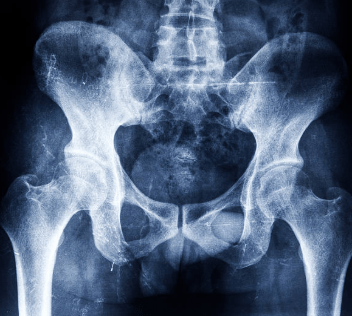

Did you know that various chronic disorders can make you suffer profoundly? For instance, people who suffer from chronic pelvic pain usually agonize in deep pain year in year out. Some even ends up losing hope of surviving form the kind of pain they are going through day after day. As a result, there are numerous health center in the country that have devoted themselves to helping these persons to manage the pelvic pains and helping in the healing processes. In the in print research, this pelvic pain research hub procedure have considerably assisted in trimming down these pains to the majority of patients across the state. The clinic have primarily devoted in treating never-ending pelvic pain condition and related dysfunction issues around pelvic floor. Did you know that people who experience this chronic disorder frequently given an assortment of treatment and diagnoses? However, depending on the medical subspecialist they see. Read on levator ani syndrome symptoms